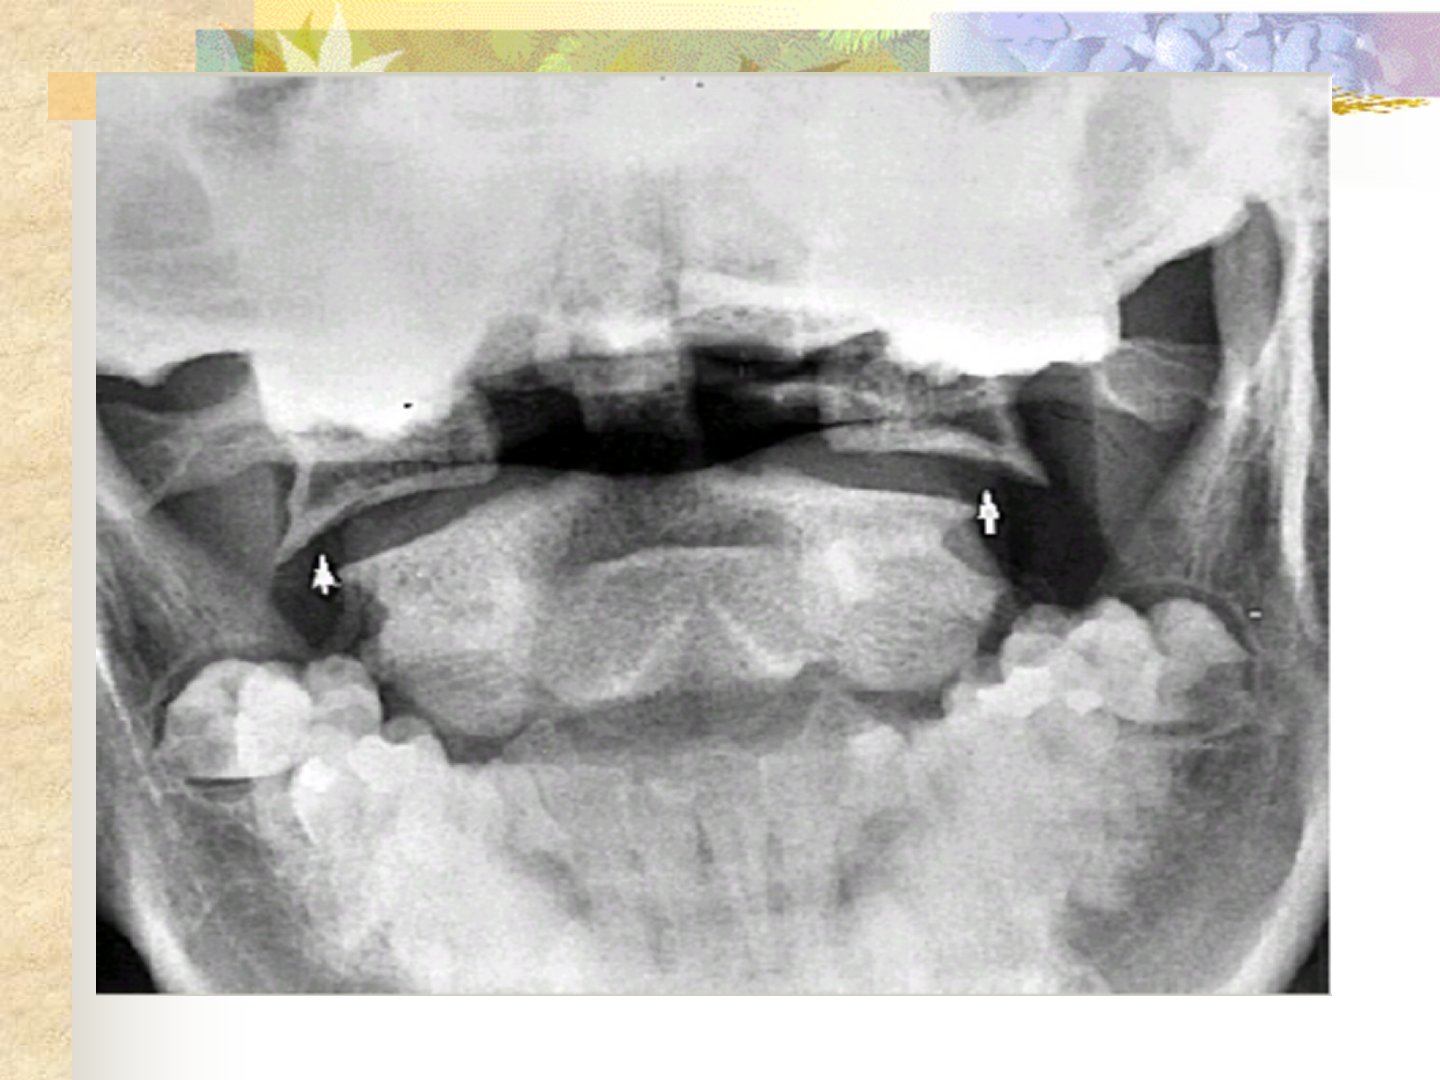

摘要:本文介绍了颈椎骨折与脊髓损伤的相关内容。颈椎骨折诊断方面包括外伤史、颈肩部疼痛及上下肢感觉运动障碍等症状通过体检和X线片、CT、MRI等辅助检查确诊。治疗上颈椎半脱位采用石膏颈围固定或脊柱融合;稳定型颈椎骨折轻度用枕颌带牵引固定严重则用颅骨牵引固定合并脊髓损伤需手术;单侧小关节脱位行颅骨牵引融合;爆破型骨折手术治疗;过伸性损伤用颅骨牵引固定;齿状突骨折视类型保守治疗或手术。脊髓损伤分为脊髓震荡、挫伤与出血、断裂、受压及马尾神经损伤等类型临床表现多样并发症包括呼吸衰竭等。治疗上保守治疗有牵引、脱水等手术治疗则针对有脊髓受压表现者尽早手术减压。